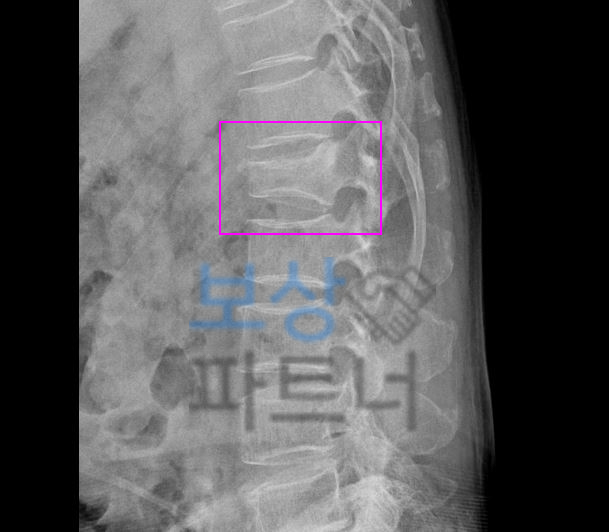

요추압박골절은 특히

척추 1번 부위의

발생 빈도가 높습니다.

요추1번은 흉추의 후만과

요추의 전만이 교차하는 부위로 미끄러지거나 허리 삐끗했을 때 검사하니 골절되거나 금갈 수 있습니다. 요추압박골절 1번척추 허리뼈골절 비수술 30% 4급 장해 보상

보상파트너로 문의해주셨던 서울시 거주 박@@님 또한 무거운 책을 드시다가 허리를 삐끗하셨다고 했는데요, 계속된 통증에 병원에 내원하여 Mri 등 정밀 검사를 받으셨고 진단 결과

L1 척추 요추압박골절

S32020 진단받으셨습니다. 박@@님은 수상일로부터 약 8주간 TLSO 허리보조기 착용하며 비수술 보존치료 진행하셨는데요, 장해보험금 청구를 위해서는

영상CD 및 영상판독지를 보면 Acute compression fracture in L1 **급성 요추압박골절 **확인됩니다. 보상파트너는 보험사도 인정할 공신력있는 상급병원 전문의로부터 후유장해 평가 받았고